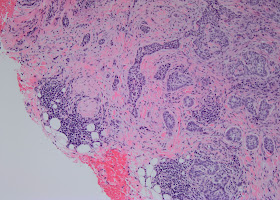

nodular & infiltrative BCC

Diagnosis: Linear Basal Cell Carcinoma